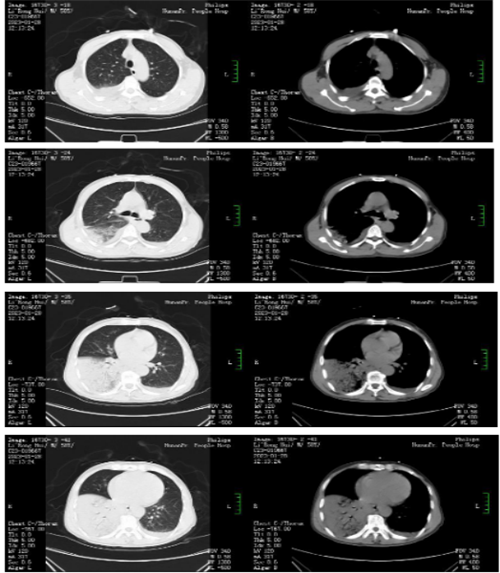

李叔叔入院后,刘翠中主任组织进行了科内讨论,考虑李叔叔病程短、症状重,对当前抗感染治疗效果不佳,需要重点考虑少见病原体的感染,于是给李叔叔安排了支气管镜检查,并送检肺泡灌洗液进行宏基因组测序(mNGS:高通量测序,一种新的病原菌精准检测手段),最终明确感染的病原体是鹦鹉热衣原体。找到病因对症治疗后,李叔叔情况逐渐好转,并于2月23日出院。